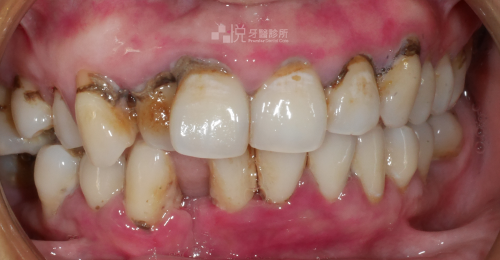

原先有嚴重的牙周病,搭配 4 次的水雷射,約 1 個月的治療時間,就有顯著改善牙周病問題。

舊有假牙侵犯到「生物寬度」(意指假牙邊緣放到牙肉底下太深的位置),導致牙齦有紅腫流血悶痛的發炎反應,本來的牙齒長度偏短、左右牙齦高度不對稱的狀況。

透過【水雷射牙冠增長術】後,讓牙齦恢復健康、和諧的外觀,並完成全口假牙的重建。